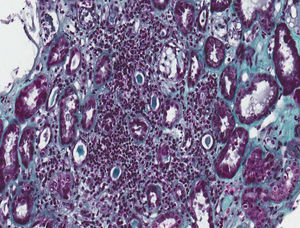

Se realizó biopsia renal, donde se obtuvieron 17 glomérulos, con fibroedema en el intersticio y un infiltrado inflamatorio a expensas de linfocitos dentro del túbulo (tubulitis), con destrucción parcial de este, con ocasional infiltración del epitelio tubular. Los túbulos presentaron vacuolización citoplasmática y descamación del epitelio intraluminal, con algunos linfocitos en su interior, escasos túbulos con presencia de células en chincheta con núcleos hipercromáticos, aumentados de tamaño y con epitelio aplanado. En la inmunofluorescencia, se detectaron ligeros depósitos granulares de IgM y C3 y en la microscopia electrónica no se observaron alteraciones relevantes. Todo esto es compatible con nefritis túbulo-intersticial aguda (NTIA) y necrosis tubular aguda leve secundaria, sin la presencia de granulomas ni nefropatíaa diabética (figs. 1 y 2).

Nefritis túbulo-intersticial y necrosis tubular aguda leve secundaria. Biopsia renal. Infiltrado inflamatorio linfocitario que afecta predominantemente al intersticio y permeación de linfocitos en el epitelio tubular con destrucción parcial de este compatible con NTIA. Escasos túbulos presentan cambios regenerativos con epitelio aplanado y vacuolización citoplasmática con núcleos agrandados de tamaño e hipercromáticos y con descamación epitelial intraluminal (necrosis tubular aguda secundaria) (tricrómico de Masson, 40×).